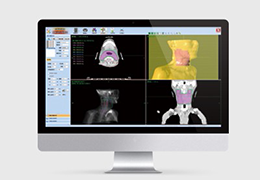

ART-Plan™ Artificial Intelligence Contouring